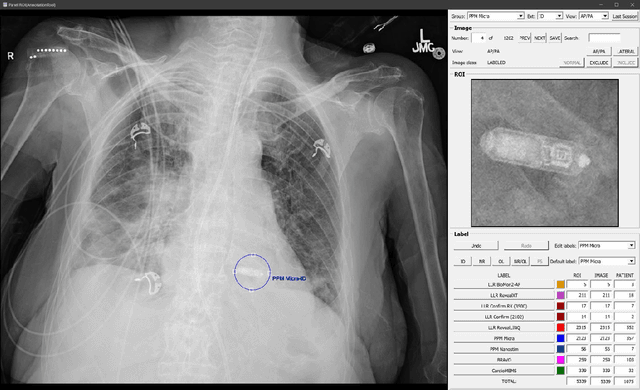

Abstract:Background & Purpose: Chest X-Ray (CXR) use in pre-MRI safety screening for Lead-Less Implanted Electronic Devices (LLIEDs), easily overlooked or misidentified on a frontal view (often only acquired), is common. Although most LLIED types are "MRI conditional": 1. Some are stringently conditional; 2. Different conditional types have specific patient- or device- management requirements; and 3. Particular types are "MRI unsafe". This work focused on developing CXR interpretation-assisting Artificial Intelligence (AI) methodology with: 1. 100% detection for LLIED presence/location; and 2. High classification in LLIED typing. Materials & Methods: Data-mining (03/1993-02/2021) produced an AI Model Development Population (1,100 patients/4,871 images) creating 4,924 LLIED Region-Of-Interests (ROIs) (with image-quality grading) used in Training, Validation, and Testing. For developing the cascading neural network (detection via Faster R-CNN and classification via Inception V3), "ground-truth" CXR annotation (ROI labeling per LLIED), as well as inference display (as Generated Bounding Boxes (GBBs)), relied on a GPU-based graphical user interface. Results: To achieve 100% LLIED detection, probability threshold reduction to 0.00002 was required by Model 1, resulting in increasing GBBs per LLIED-related ROI. Targeting LLIED-type classification following detection of all LLIEDs, Model 2 multi-classified to reach high-performance while decreasing falsely positive GBBs. Despite 24% suboptimal ROI image quality, classification was correct in 98.9% and AUCs for the 9 LLIED-types were 1.00 for 8 and 0.92 for 1. For all misclassification cases: 1. None involved stringently conditional or unsafe LLIEDs; and 2. Most were attributable to suboptimal images. Conclusion: This project successfully developed a LLIED-related AI methodology supporting: 1. 100% detection; and 2. Typically 100% type classification.